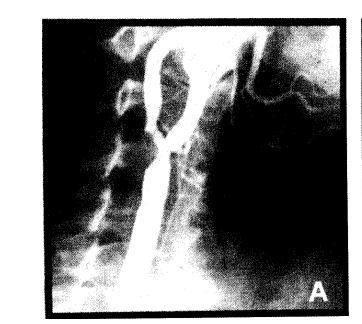

El accidente cerebrovascular es una enfermedad con alta prevalencia que en un 20%-30% se atribuye a obstrucciones carotideas y en cuyo tratamiento la endarterectomía quirúrgica ha demostrado que tiene mejor resultado en el largo plazo que el tratamiento medico. En los últimos años, en la literatura internacional se han publicado diversas series acerca de la angioplastia carotidea con muy buenos resultados. En esta serie prospectiva comunicamos 71 pacientes con 81 procedimientos de angioplastia carotidea asistida con implante de stents y en los cuales se logró éxito clínico en el 96,3%. La incidencia de accidente cerebrovascular mayor fue del 1,2%, de accidente cerebrovascular menor del 2,5%, de accidente isquémico transitorio del 1,2% y la combinación de cualquier accidente cerebrovascular o muerte a los 30 días fue del 3,7%. En la evolución alejada (14 meses de tiempo medio), la incidencia de reestenosis fue del 4,5% (3,9% por procedimiento). No hubo eventos isquémicos ipsilaterales en el seguimiento. La incidencia de eventos vasculares no relacionados con el procedimiento fue alta, posiblemente debido al grado de enfermedad vascular de la población tratada.